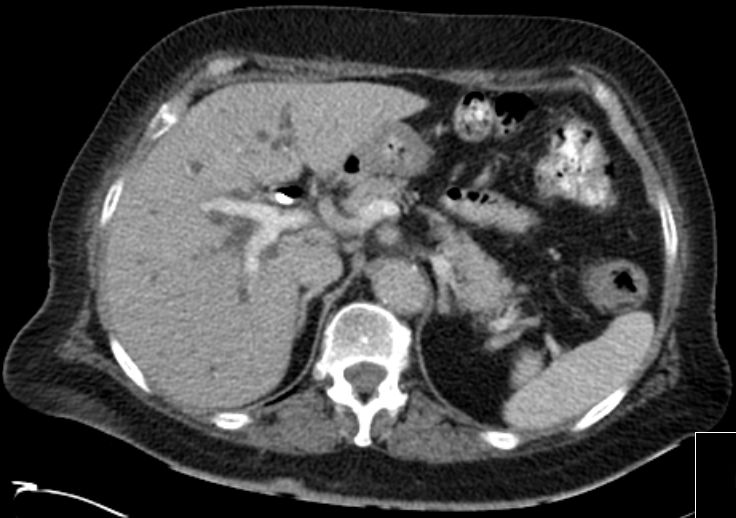

| CT | 81-jähriger Mann mit schmerzlosem Ikterus. Tumor in der Hepatikusgabel. CT nach Stent, portalvenöse Phase: Erweiterte Gallengänge des rechten Lebenlappens, RF im Leberhilus.![]() | |||